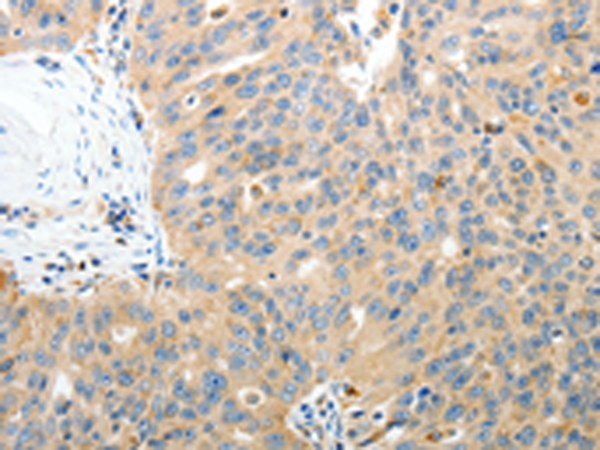

分类: 科研抗体货号: P07572别名: GBF1; GBF-1; PGES2; C9orf15; mPGES-2应用: WB,IHC反应种属: Human, Mouse